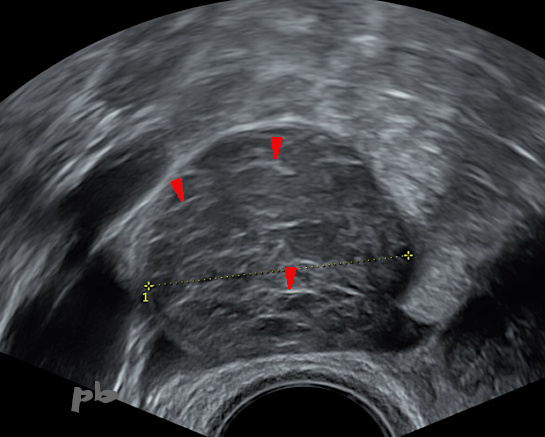

15 – Diagnostic différentiel – Kyste hémorragique fonctionnel

Patiente se présentant pour des métrorragies et des douleur pelviennes droites.

Echographie du 29/7 : suspicion d’adénomyose et kyste ovarien droit fonctionnel hémorragique typique. Fines travées hyperéchogènes internes (►).